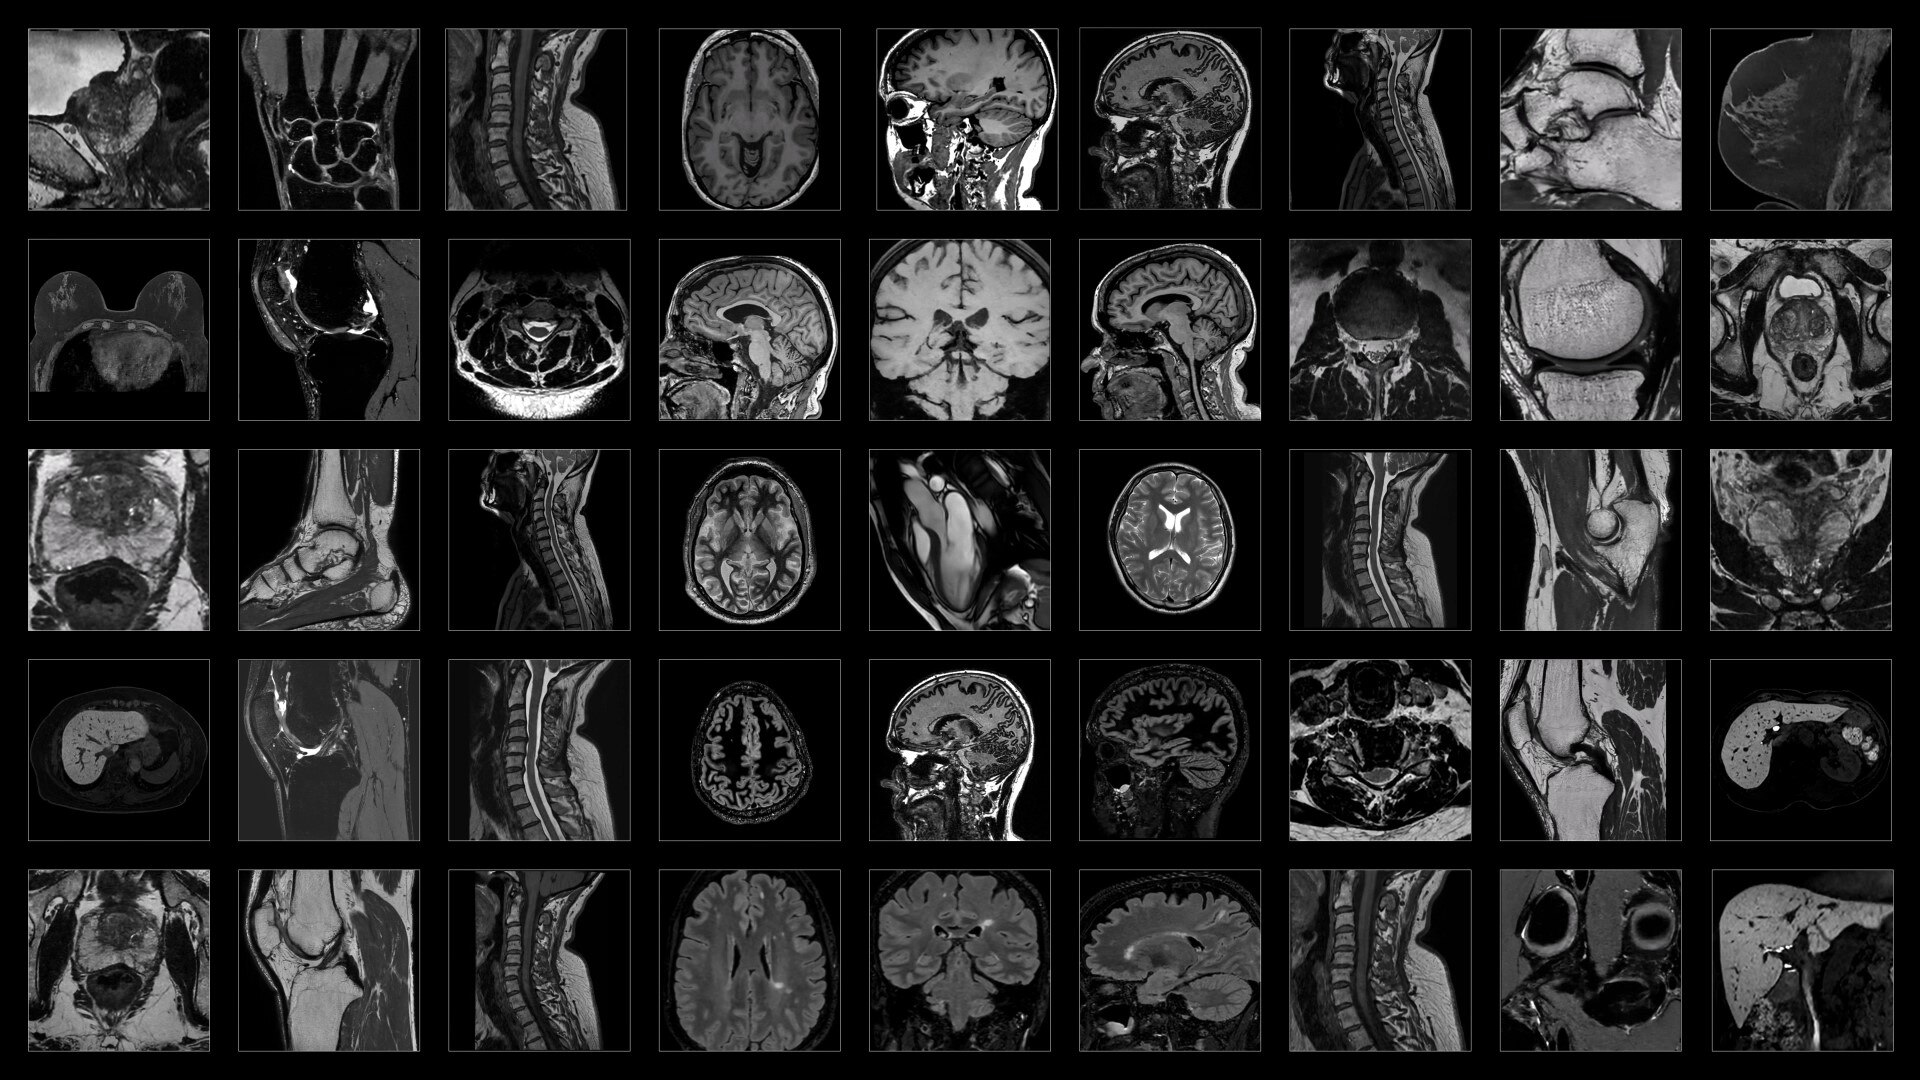

PET/CT imaging is constantly evolving

We have built a system that can evolve along with it. Omni Legend is built on a platform designed with the future in mind, so it can provide the flexibility your hospital needs to help protect your investment into the future.